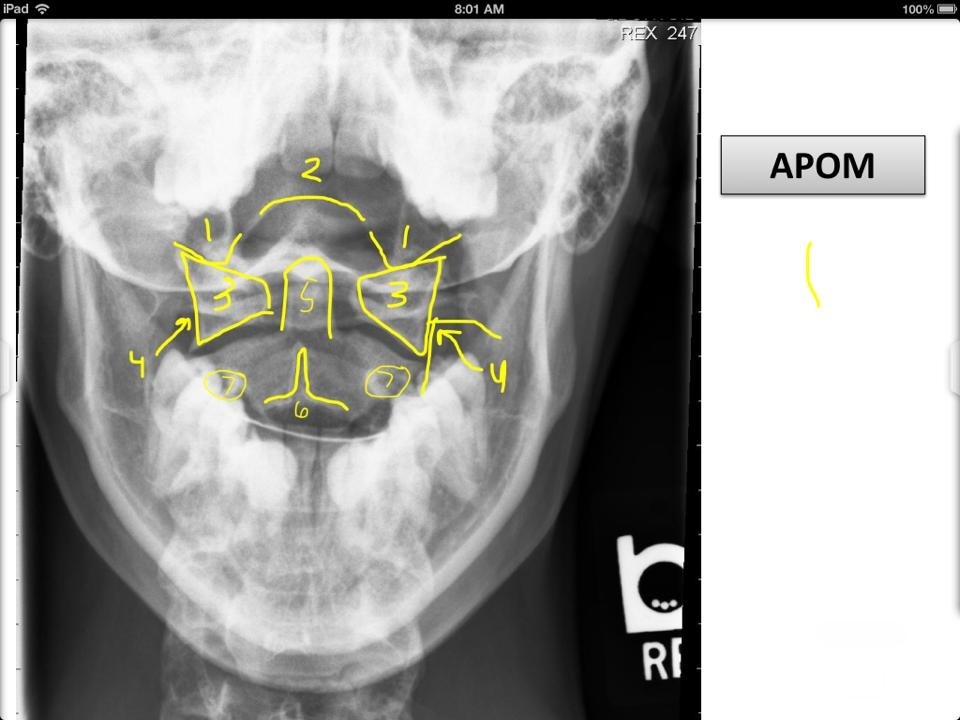

7

Q

1

A

Ocipital Condyles

8

2

Foramen Magnum

9

3

Lateral Masses of C1

10

4

C1 TVP/Lateral Mass Junction

11

5

Odontoid Process

12

6

C2 Spinous Process

13

C2 Pedicle shadow